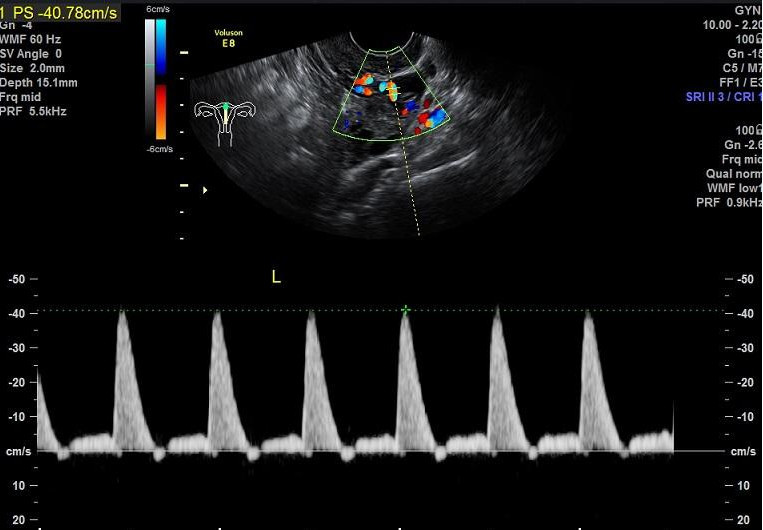

子宫是孕育生命的摇篮,子宫动脉及其分支为它提供源料,输送营养,为胚胎发育做好准备。怀孕后,子宫动脉将富含营养物质的母血送至胎盘绒毛间隙,与胎儿血液进行物质交换。子宫内膜如同种子发育的土壤,子宫动脉及其分支为摇篮和土壤提供源源不断的血供和营养,保证胚胎发育所需要的各种养分。

简单理解就是:子宫动脉是为胎儿输送成长液的轨道。如果因各种原因导致子宫动脉血供异常,阻力过大,血液灌流不足,营养供给跟不上,就会影响胚胎的着床、发芽及生长,从而引起流产。

一项基于1700多例复发性流产患者进行的回顾性分析显示复发性流产有明确原因的达63%,排除胚胎因素后,自身免疫和血栓前状态导致反复流产者所占比例最大。而孕期的血栓状态最直接的影响就是子宫动脉血流,因此不少反复自然流产的患者伴有子宫动脉血流的异常。